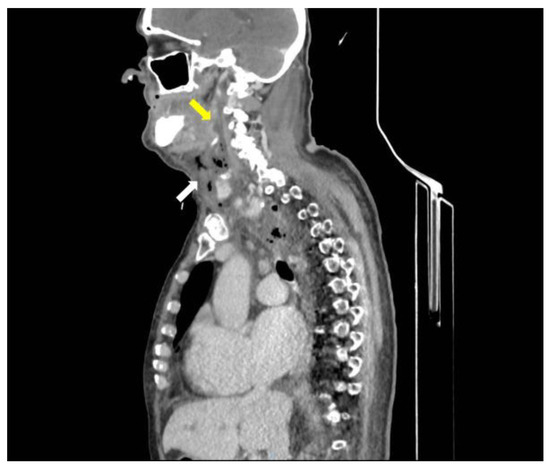

Introduction: Eggerthia catenaformis, a non-spore-forming anaerobic Gram-positive bacillus component of the human fecal microbiota has rarely been reported in human diseases. In almost every case described in current literature to date, dental diseases (abscesses, periodontitis, or caries), are the most common source of the infection which extends to the brain, cervical spaces, pulmonary parenchyma, the pleural cavity, the abdominal wall, and the abdominal cavity. Case report: An 82-year-old male Caucasian patient was admitted to our Emergency Department (ED) with a painless, right submandibular mass, dyspnea, and inspiratory stridor. A CT scan of the head, neck, and chest with intravenous contrast material revealed a retrotonsillar fluid collection. Air bubbles and minimal fluid were present from the right sub-mandibular area to the lower mediastinum between the spine, the descending thoracic aorta, and the trachea. The patient underwent surgical treatment and a broad-spectrum antibiotic. The retropharyngeal fluid collection culture showed the presence of Eggerthia catenaformis. After a first period in the Intensive Care Unit, he was admitted to a Step-Down Unit (SDU) where he underwent respiratory weaning, motor rehabilitation, and gradual oral feeding resumption. At discharge, the patient maintained the tracheal cannula as he still had impaired swallowing of solid foods. Conclusions: Here we report the first case of descending necrotizing mediastinitis in a patient with a retropharyngeal abscess, in the absence of dental diseases. Full article

Show Figures

Figure 1